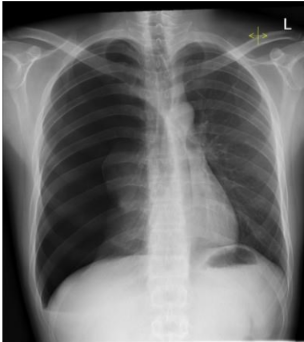

● Chest X-Ray notes hyperlucent right hemithorax, collapsed right lung, and the left tracheal

deviation as shown in the image below.